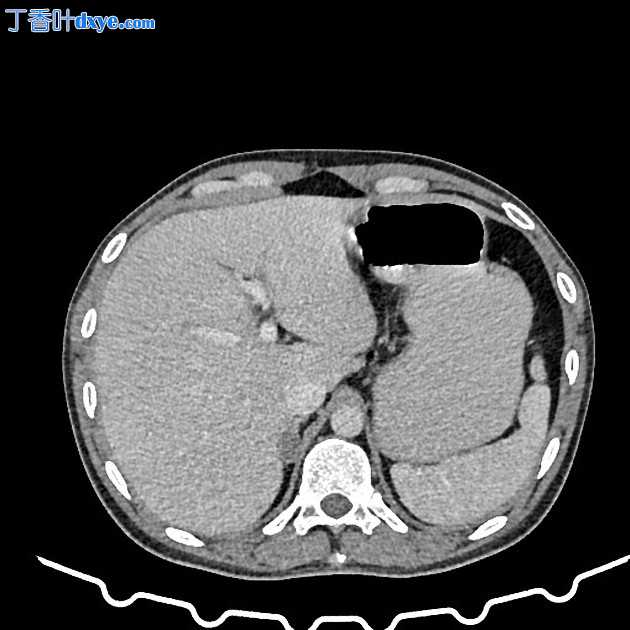

Axial C+ portal venous phase

该研究揭示了盲肠、末端、回肠远端同心增厚和变窄,回盲连接部向上拉,导致近端小肠袢扩张。

多发小肠系膜淋巴结可见明显的周围水肿和脂肪搁浅。右髂窝也可见肠系膜血管突出。

几乎没有其他可疑的粘膜充血/壁增厚区域涉及回肠。

右侧骨盆可见轻度游离液体。

右肾上极可见界限不清的低密度区,上、中极肾盏张开、受压。右肾盂可见外周高密度不规则软组织,延伸至肾盂输尿管交界处,导致轻微肾积水。在右侧骨盆输尿管交界处/上输尿管的排泄期可见造影剂轻度滞留。

左肾及输尿管无异常。

双侧肾上腺扩大,分叶状轮廓和对比后研究中的异质增强。

双侧肺的可视化切片显示两侧有多个微小的小叶中心结节。